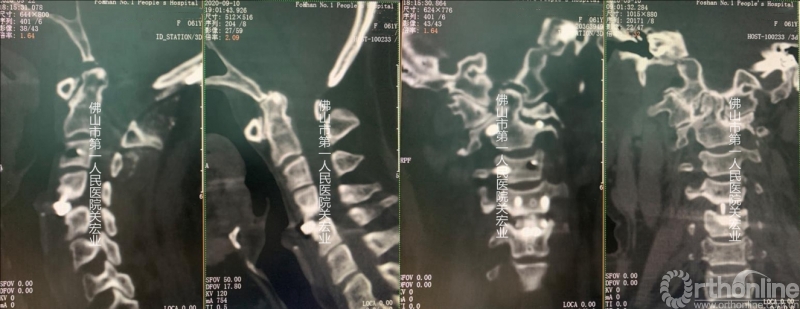

术前CT

影像学术前、术后对比